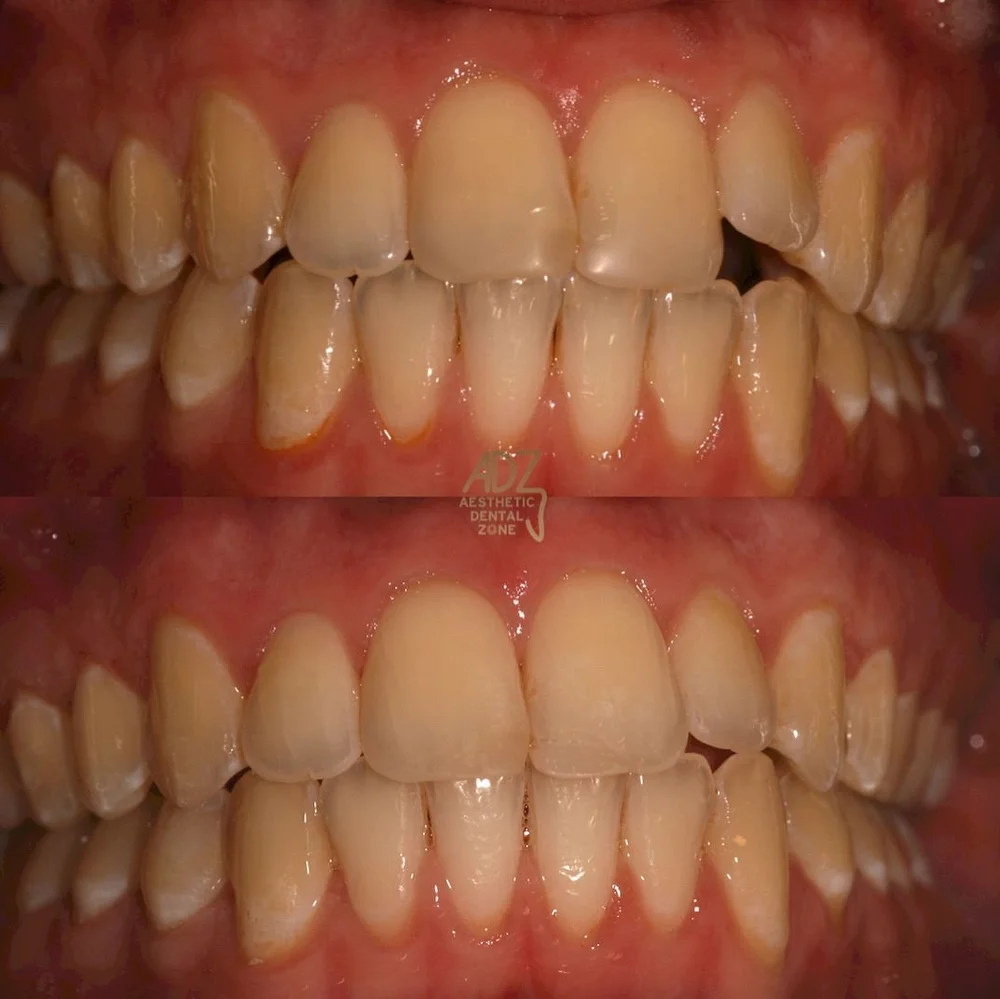

Invisalign treatment is the simple and invisible cosmetic solution to achieving the smile you desire. Avoid fixed appliances (braces) and realign your teeth with a set of our aligners.

Invisalign is an orthodontic treatment that straightens teeth using a system of clear plastic aligners fitted to the patient’s evolving bite. The clear aligners exert force on crooked teeth, gradually shifting them. Patients will be advised to change aligners every one to two weeks as the bite progresses toward an ideal outcome. The numbers of aligners needed is different for each individual.

Invisalign patients will be required to wear their aligners for 20 to 22 hours a day taking them out only to eat and brush teeth.